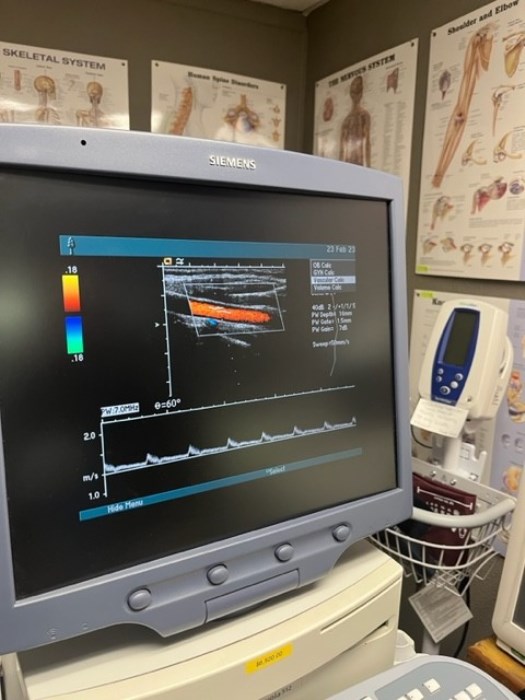

Siemens Sequioa Ultrasound

Pre-owned. In good working condition. Shown as is. Siemens Sequoia Ultrasound. DOM: 2006

Probes: 15L8w, 4V1, 10V4, 6L3, 4C1